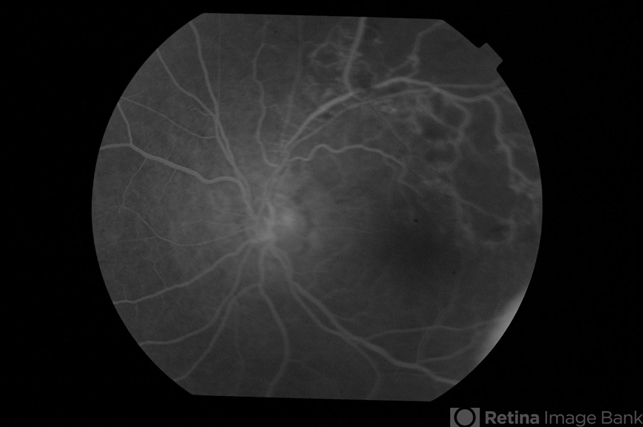

- BRVO with nonperfusion

- non-perfused branch retinal vein occlusion (BRVO)

- Late phase fluorescein angiogram in an eye with superotemporal BRVO shows delayed filling of retinal vessels and non-perfusion in the affected quadrant .